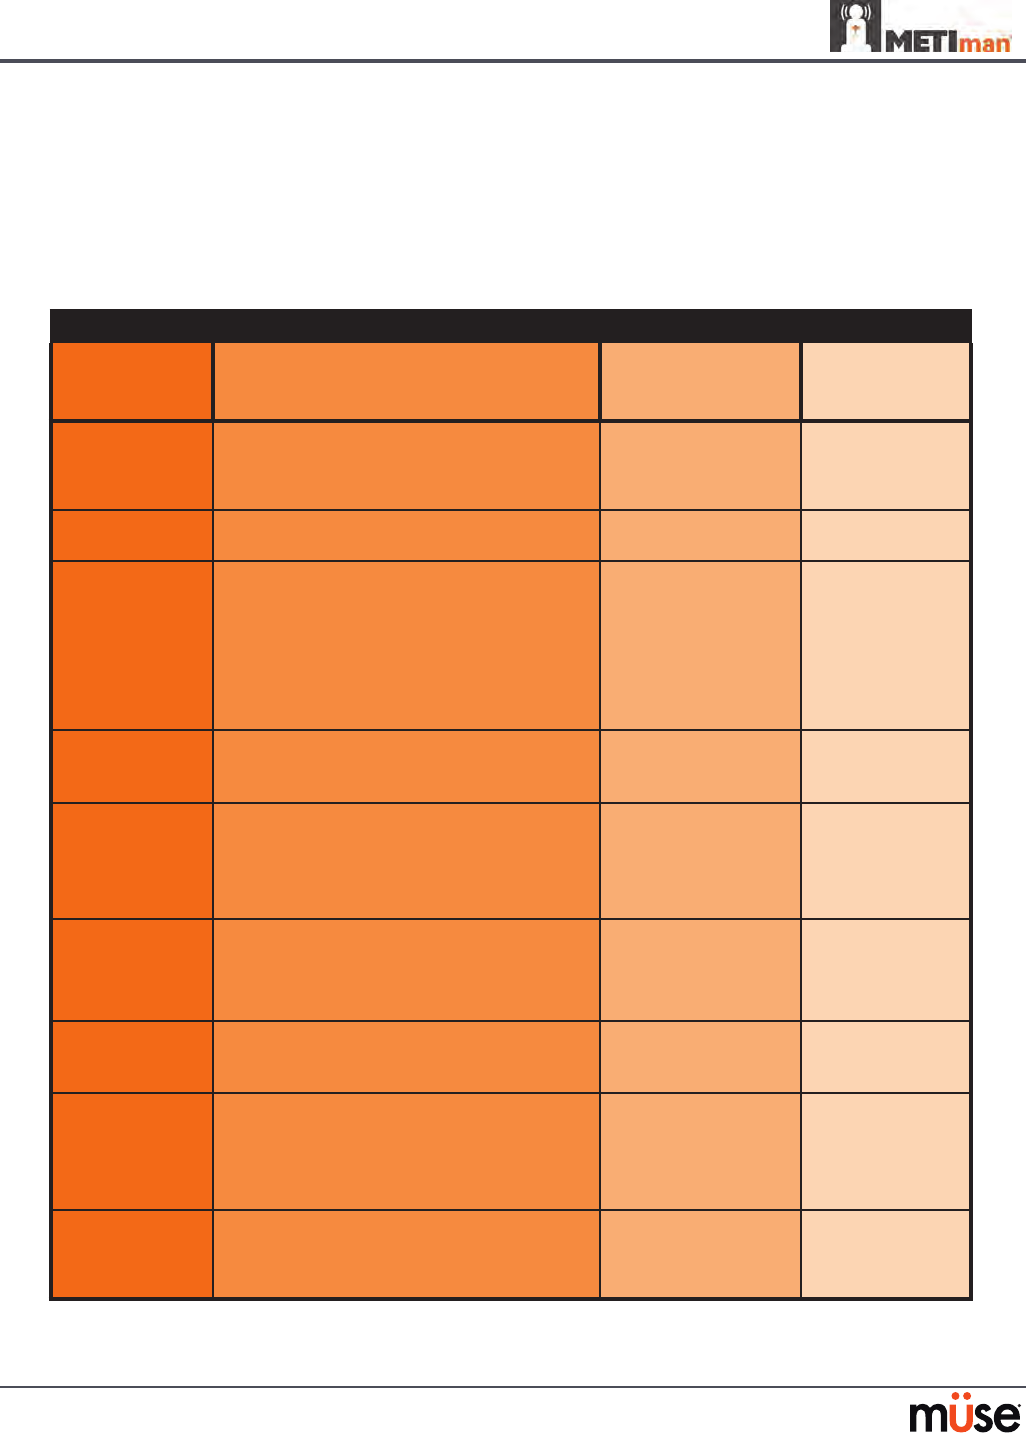

Pulmonary System

Anatomy,

Physiology and

Clinical Signs

Clinical Interventions, Patient Monitoring

and Scenarios.

Software Control

Manual Control

Spontaneous

Breathing

Normal tidal breathing and pathophysiological

conditions such as atelectasis, pneumothorax,

asthma and COPD.

None required, but

adjustable

VIEW: Respiratory

None required.

Exhaled CO2

(Prehospital only)

Measure the presence or absence of CO2 during

positive pressure ventilation.

None required. CO2 canister is

inserted

Pneumothorax or

Hemothorax

Increase in intrapleural volume, leading to

asymmetrical breathing.

None required, but

adjustable

VIEW: Respiratory

CONTROL: Intrapleural

Volume

(Left or Right)

None required.

Chest Excursion Synchronized with ventilation (spontaneous or

positive pressure ventilation). Excursion depth

proportional to tidal volume.

None required. None required.

Breath Sounds Normal and abnormal breath sounds are

independently synchronized with ventilation of

the right and left lungs. Breath sounds can be

auscultated over anterior and posterior anatomic

locations.

None required, but

adjustable

VIEW: Sounds

None required.

Bronchial

Occlusion

Completely obstructs right and/or left mainstem

bronchi, simulating a lower airway obstruction

(e.g. mucus plug). This yields an inability to

ventilate the lungs and asymmetric chest

excursion.

VIEW: Respiratory None required.

Pulse Oximetry Oxyhemoglobin saturation (SpO2) automatically

correlates with the oxygen concentration in the

lungs and the intrapulmonary shunt fraction.

None required, but

adjustable

SpO2 probe is

attached.

Arterial Blood

Gases

PaO2, PaCO2 and pH are continuously calculated,

and the Patient Status Display can be congured

to show them.

None required, but

adjustable

None required.

Venous Blood

Gases

PvO2 and PvCO2 are continuously calculated, and

the Patient Status Display can be congured to

show them.

None required, but

adjustable

None required.

139